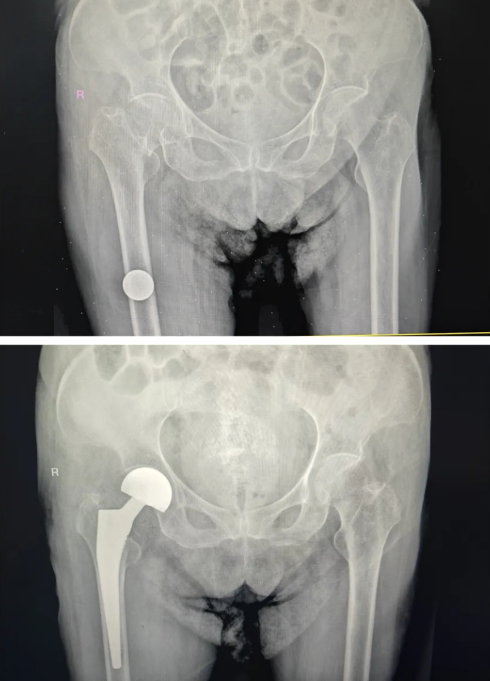

手术前后影像对比

手术当日,夏均青主任医师精准操作,团队密切配合,轻柔剥离、精准复位、稳妥固定,顺利完成人工髋关节置换术。手术创伤小、出血少、耗时短,全程生命体征平稳,手术圆满成功。

骨伤科创伤关节一病区夏均青主任医师、杨凯主治医师手术团队进行精密规划,结合患者高龄、骨质疏松、骨骼条件差的特点,依托影像学资料进行三维测量与假体精准匹配,确定最佳手术入路、假体型号与固定方式,预判术中所有风险点并制定应急预案,确保手术方案科学、精准、安全。